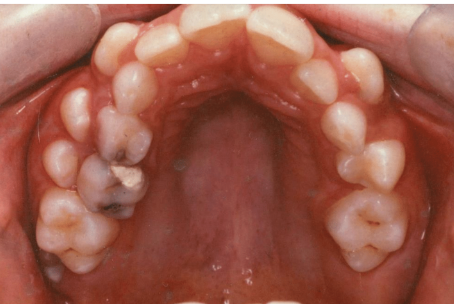

which primary teeth are still present

55, 53

63, 65

which primary teeth have been extracted early

54

64

name for forward movement of teeth into an extractions space

mesial drift

caries risk category

why (3)

high risk

early loss/extraction of primary molars

existing restorations

new carious lesions